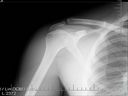

Okej, wróciłem do domu, temblak jakoś zrobiłem i uruchomiłem płytę z RTG. Pierwsze zdjęcie przejrzałem, faktycznie jest ok tak na chłopski rozum, no ale potem przełączyłem na drugie, którego lekarz nie oglądał.

http://imageshack.us/photo/my-images/818/stawbarkowy.jpg/

Czy przypadkiem nie jest złamana kość ? Oczywiście jutro kieruję się do Szpitala Wojskowego i proszę o pomoc, ale jestem po prostu w szoku...

Według mnie w tym miejscu faktyczne brak jest połączenia kostnego, zamiast tego chyba mamy tam ścięgno? http://o.elobot.pl/s/bot6/5339.jpg